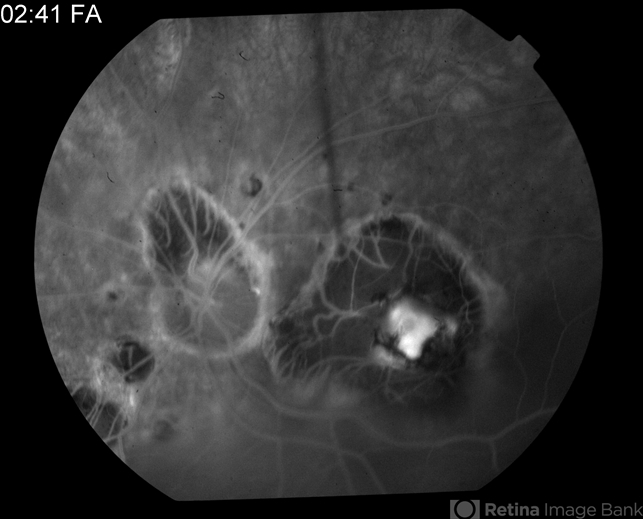

- tuberculosis, macular scar

- Tom Steele, CRA Midwest Eye Institute Indianapolis, Indiana

- Fundus camera

- 2:41 minute FA of 81-year-old male - old tuberclosis scar.